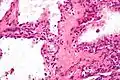

![]() صورة مجهرية تظهر ورم غدي كيسي مصلي في البنكرياس. صبغة الهيماتوكسيلين واليوزين. صورة مجهرية تظهر ورم غدي كيسي مصلي في البنكرياس. صبغة الهيماتوكسيلين واليوزين. | |

صورة مجهرية ورم غدي كيسي مصلي (تكبير عال)